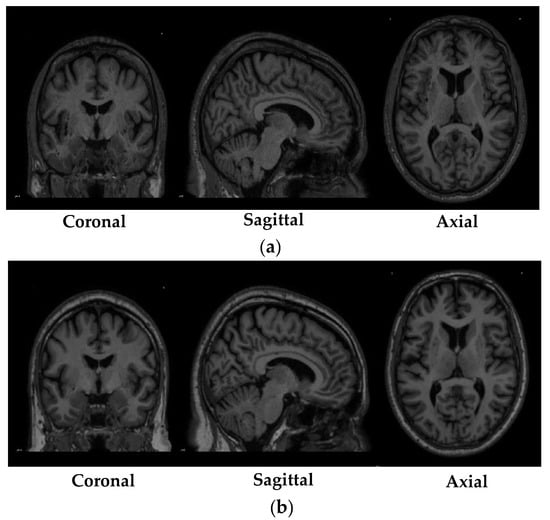

The registration of the MRI scans obtained from the PPMI database was performed using MNIPD25-T1MPRAGE-1 mm atlas created by [40,41,42]. The specifications of the MNIPD25-T1MPRAGE-1 mm atlas is described in Table 4. The registration of the MRI scans was performed using one of the most effective normalization tools known as advanced normalization tools python (ANTsPy) [43]. ANTsPy is used particularly in the field of imaging research for extracting important information from complex imaging datasets to perform preprocessing on MRI, fMRI, and SPECT data. The registration of the acquired MRI scans with the MNIPD25-T1MPRAGE-1 mm atlas was performed using symmetric normalization. Figure 2 depicts a particular MRI scan before and after the registration process.

Figure 2.

Before and after registration of a particular scan, (a) MRI scan before registration and (b) MRI scan after registration.